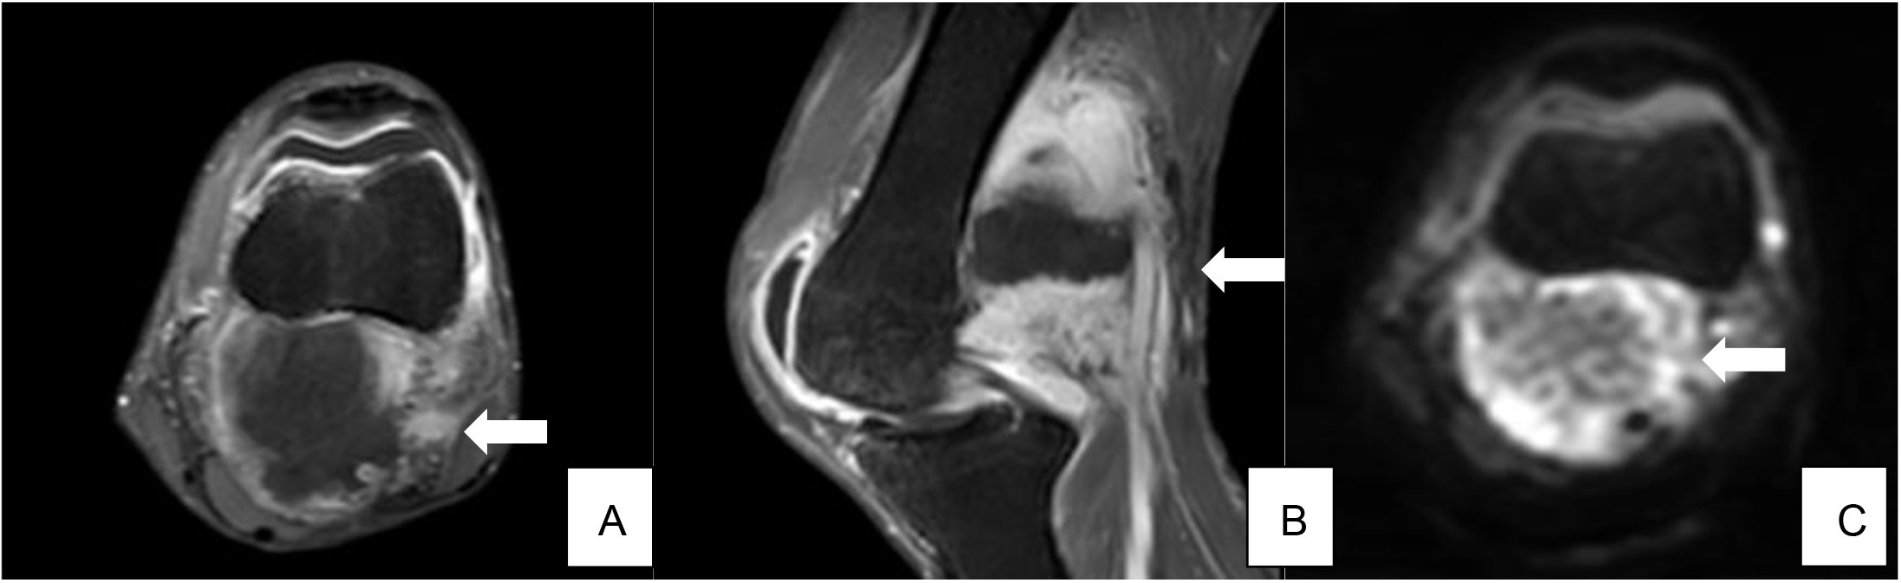

在完成7个周期化疗后约4个月,患者左下肢出现疼痛和活动受限。体格检查发现左膝后内侧上方有一坚硬肿块。下肢MRI显示左侧股骨后方有一肿瘤性肿块,表现出弥散受限和对比增强(图3)。

图3. 左大腿远端 MRI 显示股骨后侧有异质软组织肿块。(白色箭头)(A)轴向 T2 加权图像,(B)矢状 T1 加权后显现中心坏死周围增强,(C)轴向扩散加权影像显示外周可存活肿瘤扩散受限